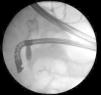

La importancia clínica de los cálculos en las vías biliares radica en su asociación con colangitis y pancreatitis aguda. La colangiografía pancreática retrógrada endoscópica (CPRE) es considerada el método terapéutico más seguro y exitoso para extraer cálculos en el conducto biliar común. No obstante, los cálculos grandes o impactados que ocupan la totalidad del conducto biliar son un reto terapéutico. Se define como cálculo biliar grande aquellos mayores de 10-15mm de tamaño. Existen muy pocos reportes que describan un cálculo único gigante (> 5cm) en el conducto biliar común. Presentamos a una paciente de 58 años que cursó con pancreatitis aguda severa y con hallazgos tomográficos de cálculo biliar impactado, dilatación de las vías biliares y colelitiasis (fig. 1). Se le realizó CPRE, encontrando un lito gigante en el conducto biliar común, ocupando hasta la confluencia de los conductos hepáticos (fig. 2). La paciente fue sometida a una colecistectomía convencional con exploración de vías biliares y hepático-yeyuno anastomosis en Y de Roux, extrayendo un cálculo coraliforme de 7×2cm (figs. 3 y 4). La paciente fue egresada sin complicaciones y se encuentra asintomática 6 meses después de la cirugía, con pruebas de funcionamiento hepático normales.